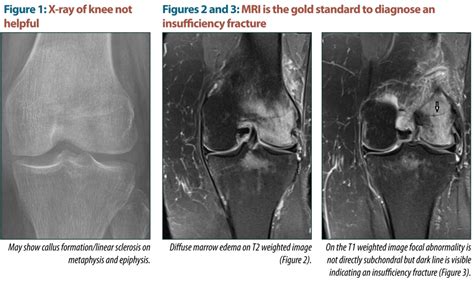

There are different causes and types of fractures. Many scouting web questions are common questions that are typically seen in the classroom, for homework or on quizzes and tests. The fractures are caused by direct violence and indirect violence. Is this hadoop mapreduce quiz helpful? Symptoms include swelling and bruising. Pain and tenderness in the bone were followed by bruising. Fractures commonly happen because of car accidents, falls, or sports injuries. Transcription means to copy to a different template (stays in the same language). To answer a question, click the button in front of your choice. Greenstick fractures are breaks in bones the period immediately after a bone fracture is critical for the proper repair of the bone and healing of the affected tissues. A sequence of events is the listing of more than one event in the order in which they occurred. Additionally, a deeper understanding of the molecular pathways involved in the bone healing process has led to emergence of serologic markers as. Which structure in the digestive system comes into direct contact with the circulatory system for transfer of nutrients into the blood? Sometimes this type of fracture is harder to detect with routine xrays. Which of the following figures correspond to possible values that pca may return for (the first eigen vector / first principal component)? This flashcard is meant to be used for studying, quizzing and learning new information. This method of immobilization is used in the fracture or dislocation of the thigh, hips, ankle, shoulder, spine, spinal.